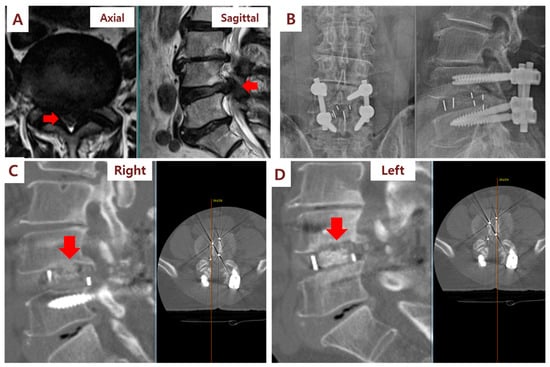

2.3. Spinal Fusion Surgery and SVF Implantation

3.2. Clinical and Radiographic Outcomes